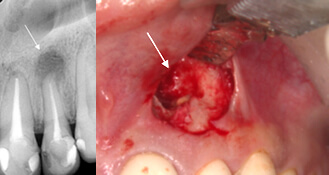

症例2. GTR

メンブレンという膜をおいて 骨が再生しやすい環境にします |

| レントゲン写真上で白っぽくなってきました。 骨が再生されはじめています。 |